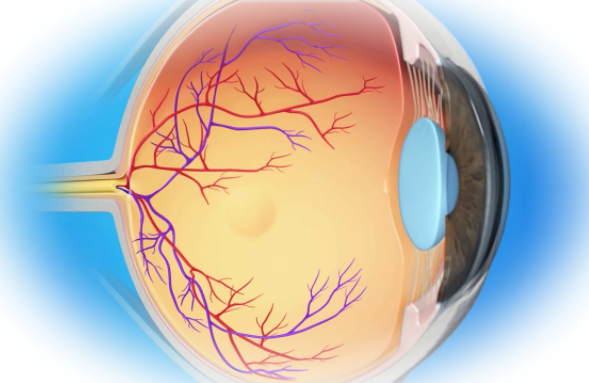

Диабетическая ретинопатия, поражение сетчатки глаза, очень часто развивается на фоне сахарного диабета. Это одно из наиболее тяжелых осложнений, которое в запущенном состоянии может привести к слепоте.

Начало заболевания обычно протекает незаметно для больного. Только при специальном исследовании глазного дна обнаруживается поражение сосудов сетчатки, отек макулы, которые присутствуют у подавляющего большинства больных. Заболевание прогрессирует, а больной поначалу даже не подозревает об этом.

Признаки диабетической ретинита обычно появляются в определенной последовательности: становятся шире просветы сосудов, увеличивается кровоток, происходит закупорка капилляров, образуются микроаневризмы, в глазу возникают кровоизлияния, капилляры разрушаются, что приводит к атрофии сосудов глаза. Как следствие — кислородное голодание сетчатки, отек макулы и постепенное разрушение ткани.

Ретинит может сопровождаться осложненими, такими как вторичная глаукома (повышение внутриглазного давления), гемофтальм (кровоизлияние в полость стекловидного тела), катаракта (помутнение хрусталика), расслоение сетчатки, отслойка сетчатки, слепота.